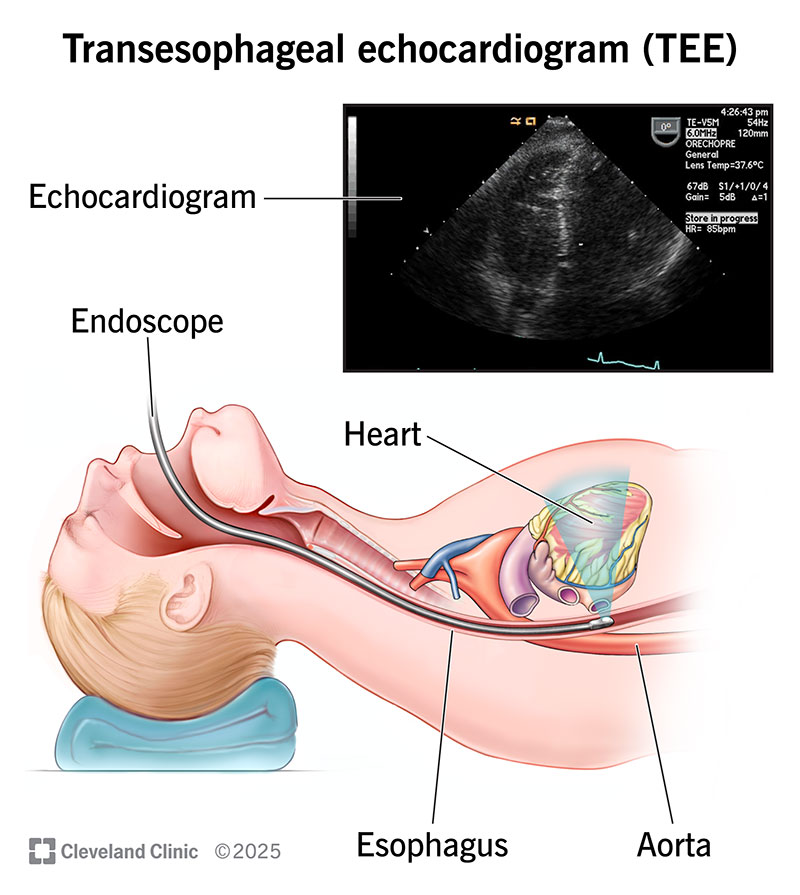

健康+医学 Transesophageal Echocardiography Transesophageal Echocardiogram (TEE)の詳細情報

Transesophageal Echocardiogram (TEE)。Transesophageal Echocardiography-Guided Extracorporeal。Transesophageal Echocardiography in Critical Care | Current。

The role of transesophageal echocardiography in clinical use

題名:PracticalApproachtoTransesophagealEchocardiography,4thed.

著者:A.C.PerrinoJr.&S.T.Reeves(eds.)

出版社:WOLTERSKLUWER

ISBN:978-1-4963-8347-1

ページ数:643pp.

出版年:2020年

定価24,739円(本体22,490円+税)

題名:PracticalApproachtoTransesophagealEchocardiography,4thed.

著者:A.C.PerrinoJr.&S.T.Reeves(eds.)

出版社:WOLTERSKLUWER

ISBN:978-1-4963-8347-1

ページ数:643pp.

出版年:2020年

定価24,739円(本体22,490円+税)